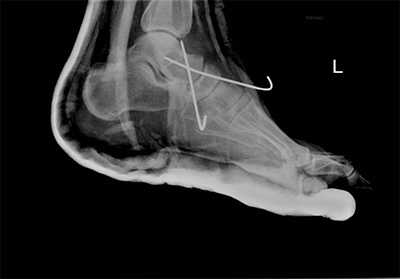

Рентгенологическое исследование

Для диагностики повреждения сустава Шопара делают рентген, КТ и МРТ. На передне-задней рентгенограмме определяют величину пяточно-кубовидного угла. Проводят одну касательную к наружному краю кубовидной кости и вторую касательную к наружному краю пяточной кости. В норме угол между касательными колеблется в пределах от 0 до 5°. Увеличение угла свидетельствует о нарушении стабильности пяточно-кубовидного сочленения. КТ во фронтальной и сагиттальной плоскостях позволяет выявить дефект суставных фасеток, смещение костей при вывихе и фрагментацию костей при переломе. КТ, по сравнению с рентгенографией, является более информативным методом диагностики. МРТ позволяет выявить дефекты отдельных связок.

Рис. 8. Переломо-вывих в суставе Шопара

Рис. 9. Переломо-вывих в суставе Шопара